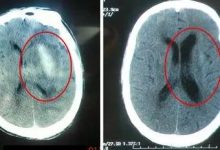

体验者:陈阿姨 年龄:七十八岁 症状:全身瘫软无力,双脚红肿 医院检查:大面积脑梗脑萎缩 八月八号下午,天气还是很炎热,陈阿姨由女儿抱进来,当时全身无力,两腿瘫软,两脚肿得像面包一样,又红又亮。陈姐拿着医院的CT片和检验报告单让我看:“医生检查说我妈是大面积脑梗脑萎缩,本来要输液的,朋友让我们来原始点交流中心看一下”我告诉她脑梗脑萎缩不是造成瘫软无力的原因,阿姨这是受了寒凉才会出现这些症状的,陈姐瞪大了眼睛说:“我们上午刚在医院拍的片子,确实是大面积脑梗脑萎缩”我告诉她“像阿姨这么大年纪的老人,很多都有脑梗脑萎缩,只要没有被寒凉所伤,是不会瘫痪的”。先让老人喝了一杯浓姜汤,然后三个人帮忙让老人趴下,开...

西医认为 脑梗死是指血液中的各种栓子(如心脏内的附壁血栓、动脉粥样硬化的斑块、脂肪、肿瘤细胞、纤维软骨或空气等)随血流进入脑动脉而阻塞血管,当侧支循环不能代偿时,引起该动脉供血区脑组织缺血性坏死。症状以猝然昏倒、半身不遂、言语智力障碍为主。 中医指的中风又名卒中,是以突然出现口眼㖞,言语不利,半身不遂,甚则猝然昏倒,不省人事为特征的病证。因病起急骤,症见多端,变化迅速,与自然界中风性善行数变的特性相似,故古代医学家以此取象比类称为中风又因其发病突然,也称为“卒中”。病因主要为1.正气不足,风邪入中。2.劳倦内伤,阴阳失调。3.饮食不节,痰湿阻络。4.五志过极,气血逆...

2018年6月14号妈妈中午睡醒午觉后发现自己的腿不像以前那么灵活,15日发现手有点伸不直,感觉有点不对劲,随后6月17号在潍坊某乡镇医院做了脑部CT检查,初步诊断是脑梗,随后6月18号女儿将母亲接到烟台。 6月19号在烟台某医院再次做检查确认,医生根据先前拍的CT片子发现脑部有积水,建议做核磁共振进一步检查,检查完后大夫给开了一些口服的西药和点滴输液。女儿听说这种情况后就和自己的哥哥和父亲商量用保守疗法给母亲调理身体,也就是用原始点疗法,因为女儿自己学习了原始点,所以原始点的观念都能接收,经过和爸爸、哥哥商量后同意用原始点疗法。 6月20号带自己妈妈来原始点爱心之家接受原始点调理,调...